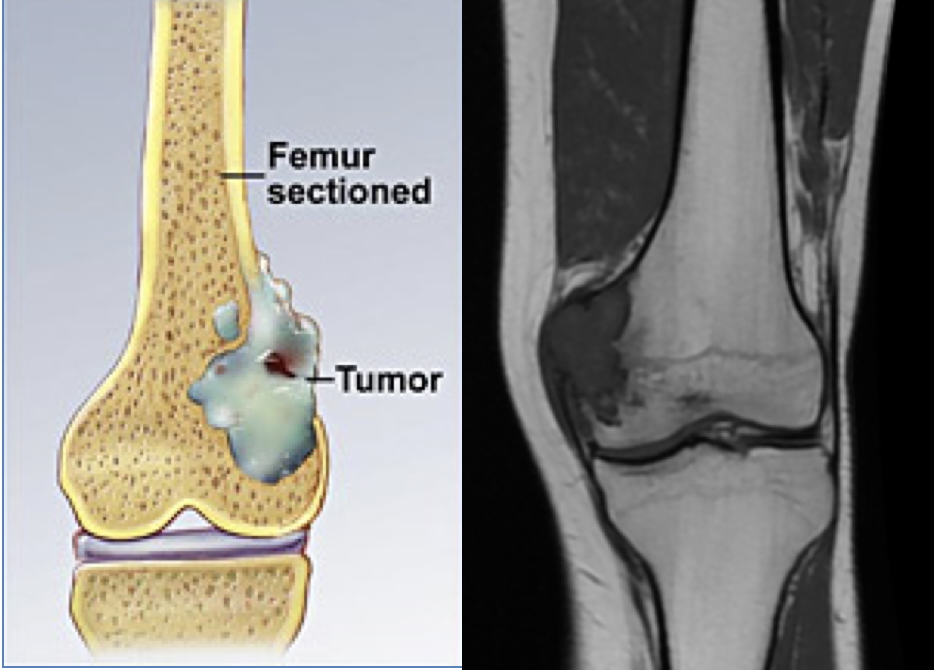

- Bone-forming tumour with dysplastic osteoblast activity

- Typically arises in metaphyseal regions of long bones

- Codman’s triangle: periosteal elevation due to subperiosteal tumour spread

- Marrow invasion common

- Sites: knee and shoulder (distal femur/proximal tibia or humerus)